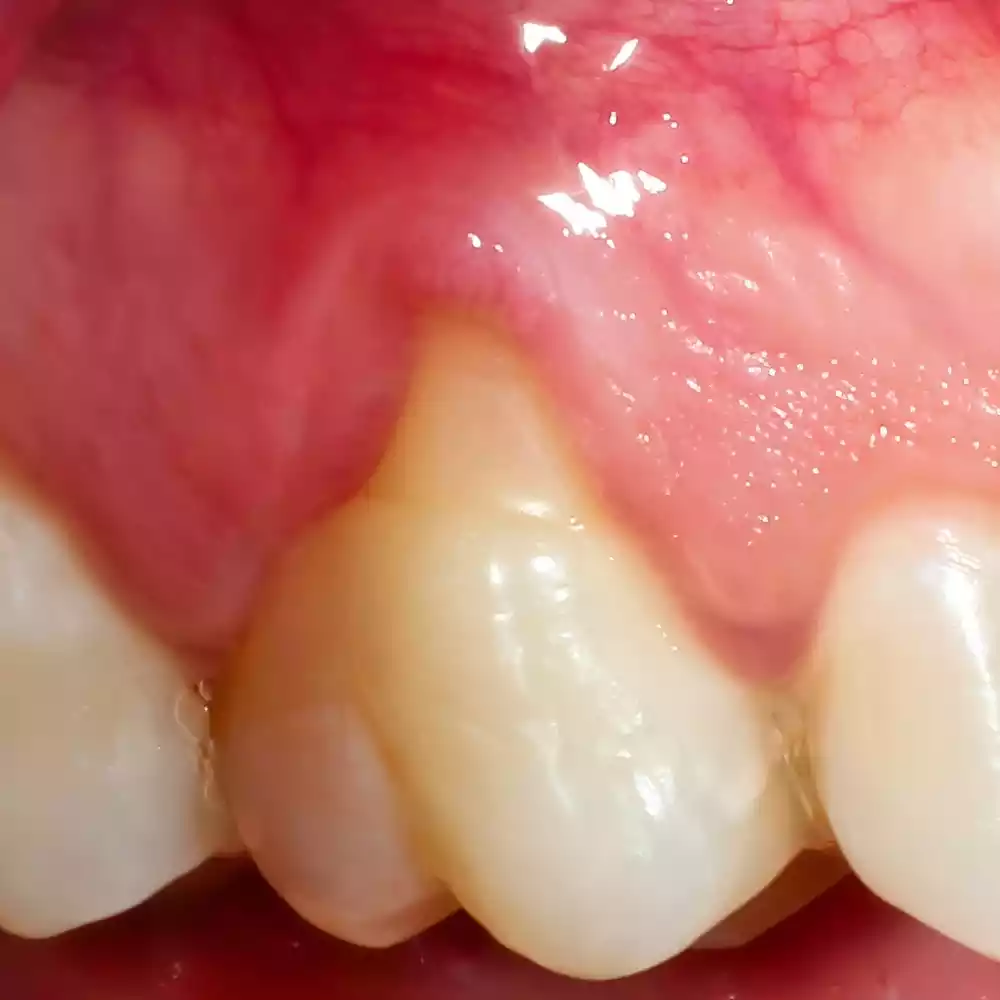

Receding gums, or gingival recession, occur when the gum tissue surrounding the teeth pulls back, exposing more of the tooth or its root. This condition can create gaps or pockets between the teeth and gum line, making it easier for disease-causing bacteria to build up. If left untreated, gums receding can lead to serious damage to the supporting tissue and bone structures of the teeth, ultimately resulting in tooth loss.

If your teeth appear longer than they used to, it may be a sign that your gums are receding. This is because the gum tissue is pulling away, making more of the tooth visible.

As gums recede, the roots of your teeth may become exposed. This can lead to sensitivity and discomfort, especially when consuming hot, cold, sweet, or acidic foods and drinks.

Pay attention to the texture and appearance of your teeth. Receding gums can cause notches or small indentations near the gum line due to enamel erosion.